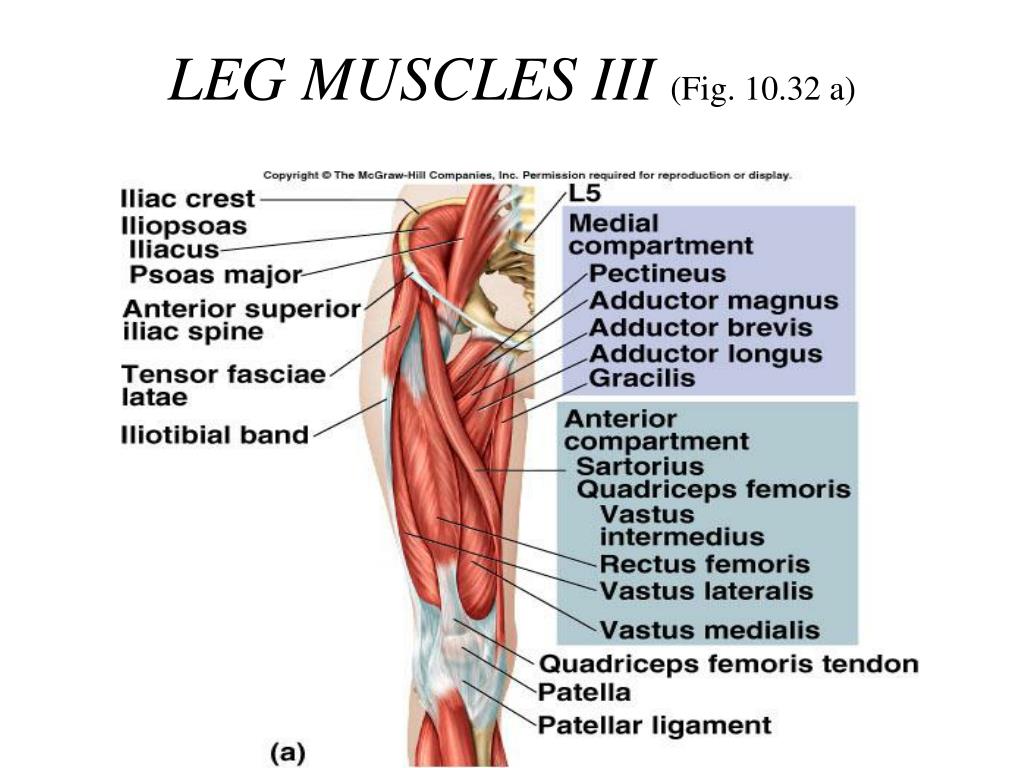

Анатомия и Функции Мышцы Adductor Magnus